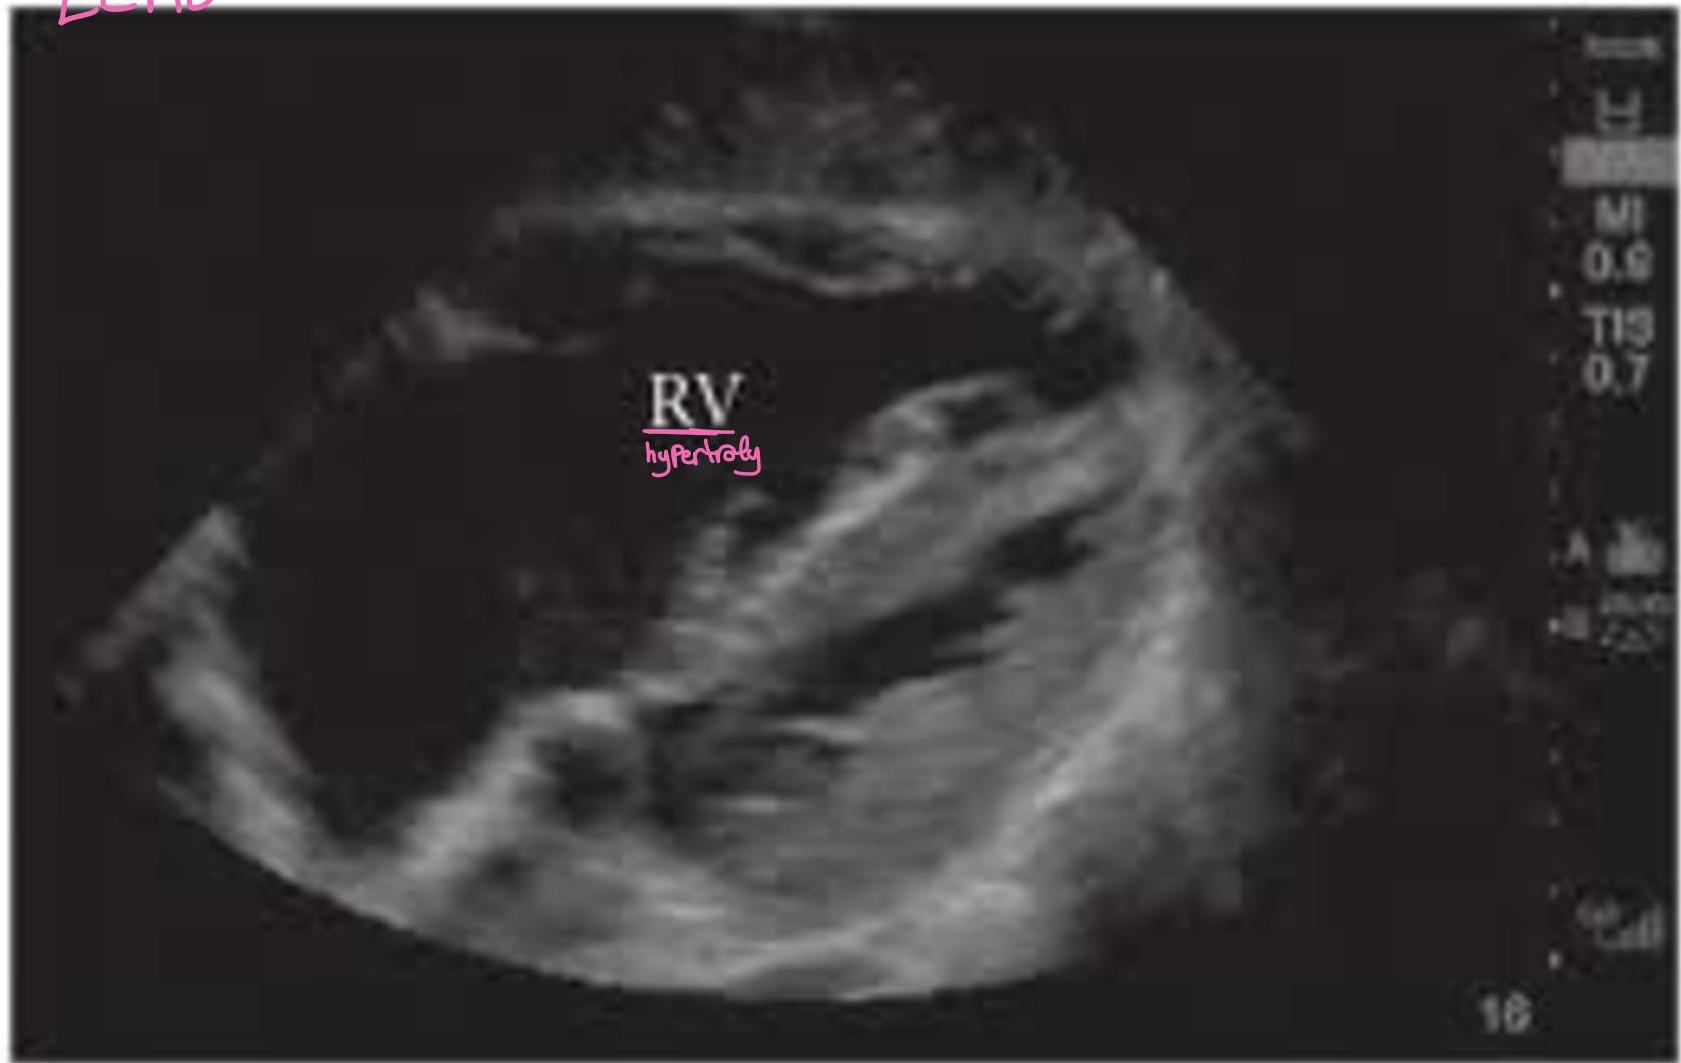

Case 1: Pulmonary Embolism (PE)

- Presentation: 62F, 3 weeks post-right THA, admitted for COPD exacerbation. Sudden onset L-sided chest pain (8/10), pleuritic, O2 sat drop (94% â 88% on 2L NC).

- Vitals: Afebrile, HR 120, BP 110/70, RR 28.

- Exam: Accessory muscle use, EAE, loud S2.

- Labs: Positive D-dimer, Troponin 0.12 (Normal < 0.04), BNP 520.

PE

- S1Q3T3: Present in only 20% of PE.

- Management Plan: Give heparin (âheforinâ [sic]) and send to CT.

Wells Score & PE Management

- Treatment: Anticoagulation (Heparin/LMWH). Thrombolytics in hypotensive/massive PE. IVC filter if bleeding risk.